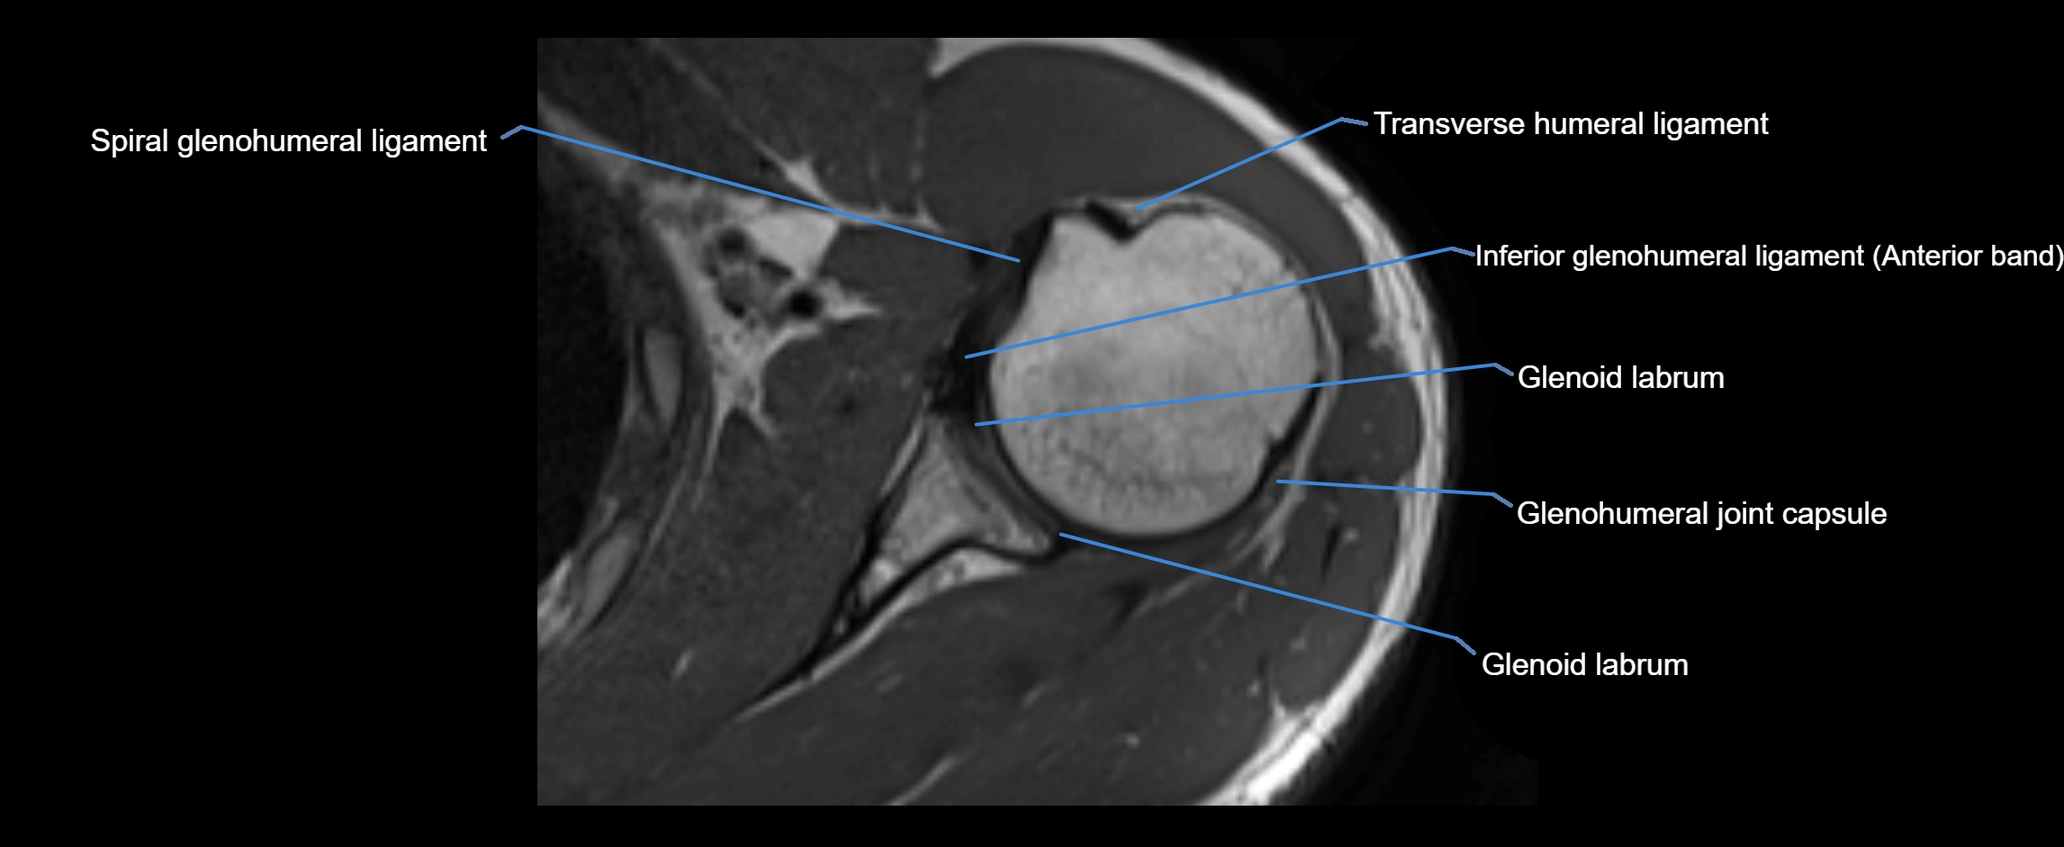

MRI images

image